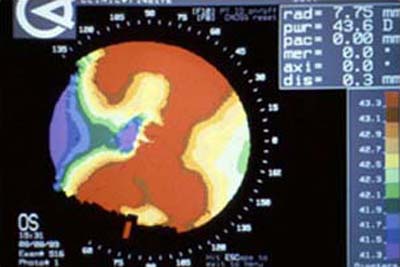

Con la difusión de la cirugía refractiva a finales de los años 70 y comienzos de los 80, fué necesario mejorar la metodología clínica existente para medir la superficie anterior de la córnea. Basados en el Queratómetro, se desarrollaron los Fotoqueratoscopios para poder capturar la imágen de los anillos del Disco de Placido reflejados sobre la córnea,pudiendo así, apreciar en forma cualitativa, distorsiones inherentes a una forma de córnea individual; ( foto N° 1)

Debido a que clínicamente era necesario poder cuantificar las distorsiones percibidas, se desarrollaron los Videoqueratoscopios que utilizan métodos computarizados para capturar la información de la imágen queratoscópica y reconstruir a partir de ella la superficie anterior de la córnea, graficandola de una manera util y facil de entender para el médico oftalmólogo. Esta técnología es conocida como Topografía Corneal.

Con esta metodología, los poderes altos de la superficie corneal son representados en colores cálidos como el amarillo, naranja y rojo (Foto 2) mientras que las áreas de bajo poder se las representa en colores más frios como el verde y el azul. ( Foto 3), facilitandose así visualización de los efectos de la cirugía refractiva y la comprensión de sus resultados ( Foto 4 y 5)